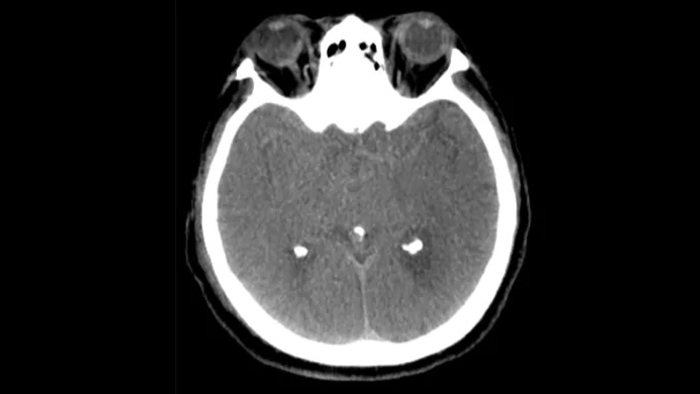

Tres SmartCT

Visualización similar a una TC

SmartCT Soft Tissue  genera una visualización de los tejidos blandos similar a la de una TC y apoya el diagnóstico del accidente cerebrovascular de tres maneras. Una exploración sin contraste ayuda a detectar los cambios isquémicos tempranos. Una exploración de fase temprana ayuda a identificar la oclusión proximal. Una exploración con contraste de fase tardía ayuda a detectar colaterales.

Control periprocedimiento de hemorragias

SmartCT soft tissue

Use las imágenes de SmartCT Soft Tissue (similar a una TC) de la suite Neurovascular para comprobar el éxito del tratamiento e identificar hemorragias.